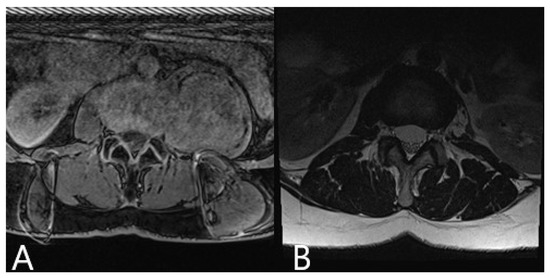

| 8 | M | 51 | Herniated disc T8/9 with myelopathy | Back pain, paraparesis 3/5, urinary incontinence | 1. Partial resection of the herniated disc via posterior approach with right costotransversectomy 2. Resection of the remaining disc via left retropleural approach 3. Stabilization T8-9 | No | No pain and no deficits following surgery |

| 9 | F | 52 | L2 Neurinoma | Back and hip pain | Resection of neurinoma via left retroperitoneal approach | No | No pain, no deficits, and no tumor recurrence at follow up |